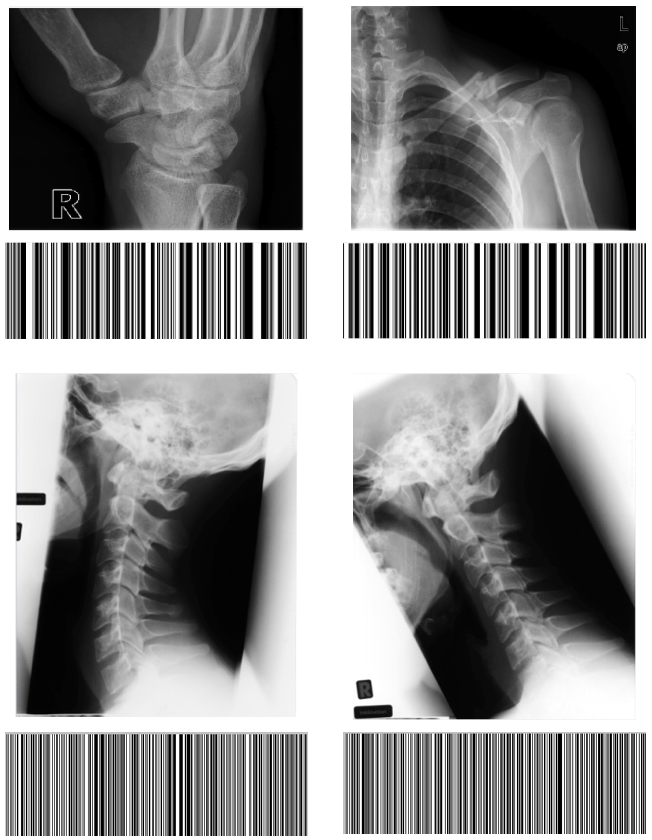

Refer to caption

Fig. 3: Generated Gabor Barcodes for four images from IRMA database